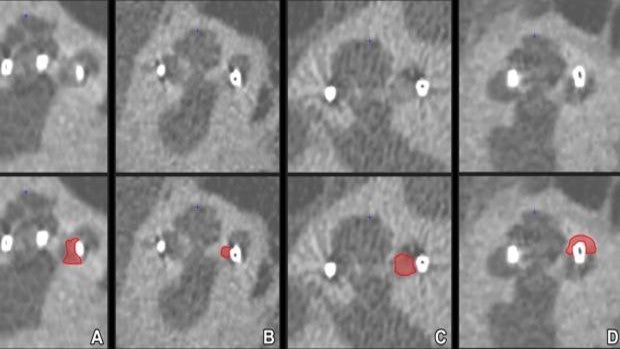

La implantación de un dispositivo coclear es un medio habitual para tratar la pérdida auditiva grave. El dispositivo consta de una parte externa que se coloca detrás de la oreja y una segunda parte implantada quirúrgicamente debajo de la piel que estimula los nervios en la cóclea. Esta es una estructura en espiral llena de líquido en el oído interno que transmite el sonido a través de los nervios sensoriales al cerebro. Los implantes cocleares, no hacen que el paciente recupere la audición normal, pero pueden ayudar al paciente a reconocer palabras y el habla. Las posibles implicaciones clínicas de la formación de un hueso nuevo hacen que sea deseable visualizar y posiblemente prevenir su desarrollo, pero aún no se ha descrito la detección en vivo o dentro del cuerpo. «Estos cambios sutiles son difíciles de detectar, en particular estando cerca de un implante metálico, ya que este, causa interferencias en las imágenes de las tomografía computarizadas», afirma el coautor principal del estudio, Floris Heutink, de la Universidad de Radboud en Nijmegen, Países Bajos. «Sin embargo, la disponibilidad de un escáner de TC de ultra alta resolución, nos animó a investigar esto proceso». Heutink y sus equipo utilizaron TC de resolución espacial ultra alta (UHRCT) para evaluar la formación de hueso nuevo y sus implicaciones en 123 pacientes con implantes cocleares. De los 123 pacientes, 83 (68%) tenían formación de hueso nuevo, predominantemente localizado en la base de la cóclea, durante lo cuatro años siguientes del implante. Los investigadores pudieron detectar la formación de hueso nuevo «en vivo» utilizando UHRCT. De los 123 pacientes, 83 (68%) tenían formación de hueso nuevo, predominantemente localizado en la base de la cóclea, durante lo cuatro años siguientes del implante. La pérdida de audición residual a largo plazo fue significativamente mayor en el grupo con formación de hueso nuevo. «Como indican los resultados de nuestro estudio, existe una correlación entre la formación de hueso nuevo y la pérdida auditiva residual a largo plazo», afirmó el coautor del estudio Berit M. Verbist, MD, Ph.D., de los Departamentos de Radiología de Radboudumc y Leiden. Centro Médico Universitario de Leiden, de los Países Bajos. La formación de un hueso nuevo alrededor del electrodo del implante coclear tiene una serie de consecuencias negativas debido a sus efectos sobre el dispositivo y las estructuras que lo rodean. Puede afectar la propagación de la corriente eléctrica dentro de la cóclea, lo que lleva a un ajuste complejo del dispositivo, a la interacción de canales y un peor resultado auditivo general. También podría complicar futuras terapias como la terapia génica para restaurar la función coclear. «Por último, pero no menos importante, la formación de hueso nuevo puede dificultar una posible cirugía del reimplante», añadió Verbist. Los investigadores observaron que las mejoras en el diseño y las técnicas quirúrgicas han hecho que la implantación coclear sea habitual para un número cada vez mayor de personas con pérdida auditiva de severa a profunda. Este aumento de pacientes hace que sea necesario, un método para detectar y controlar la formación de hueso nuevo en vivo sea más necesario que nunca. «Esta técnica será una herramienta valiosa para obtener información sobre el motivo, los tiempos y la fisiopatología de este proceso y tal vez se use para evaluar tratamientos aún por desarrollar contra la formación de hueso nuevo», finalizó Heutink.Fuente Salud https://ift.tt/3rIGqwJ